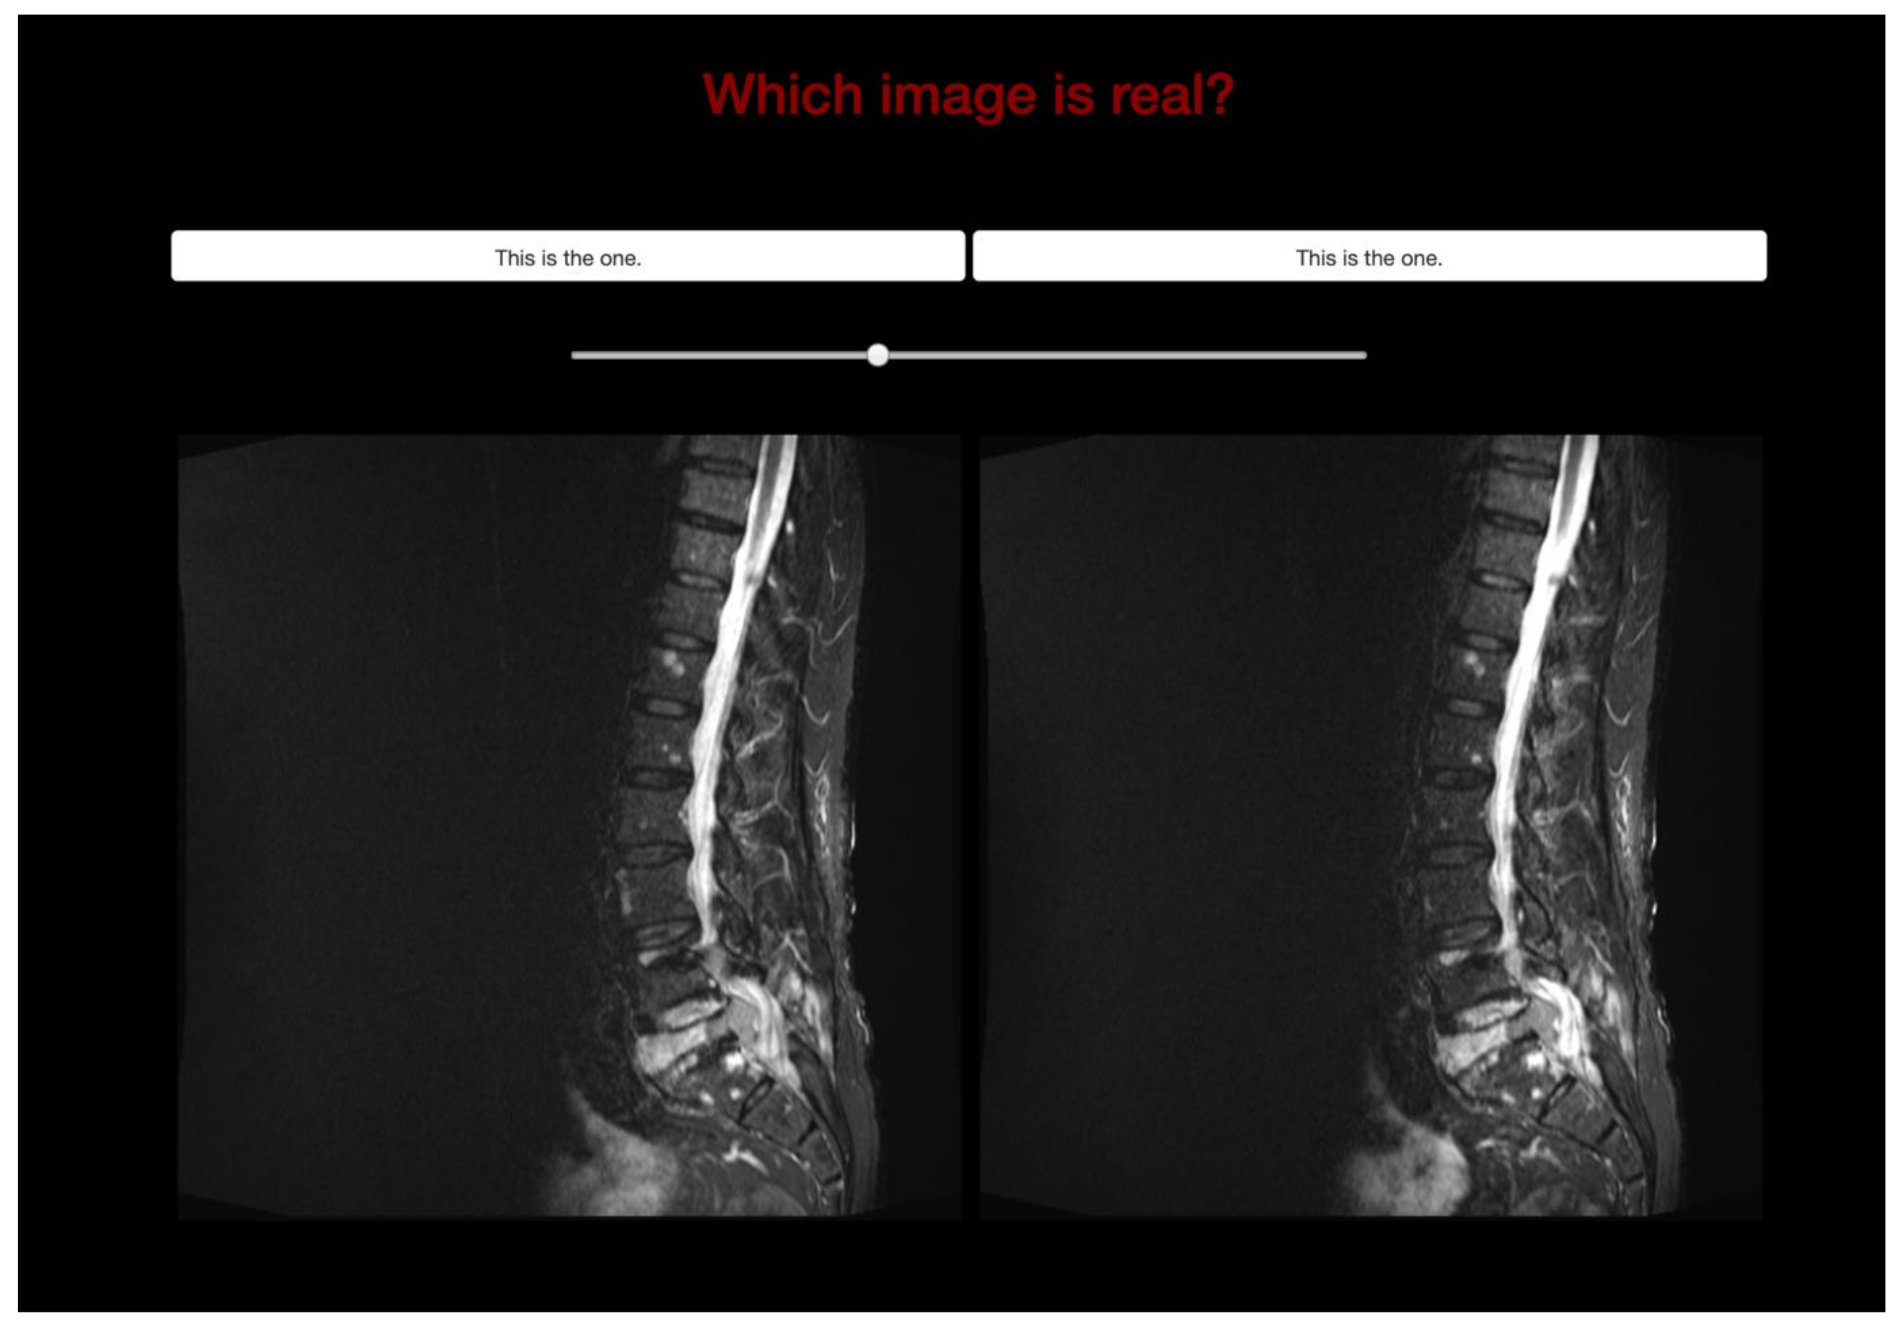

2.4. Validation